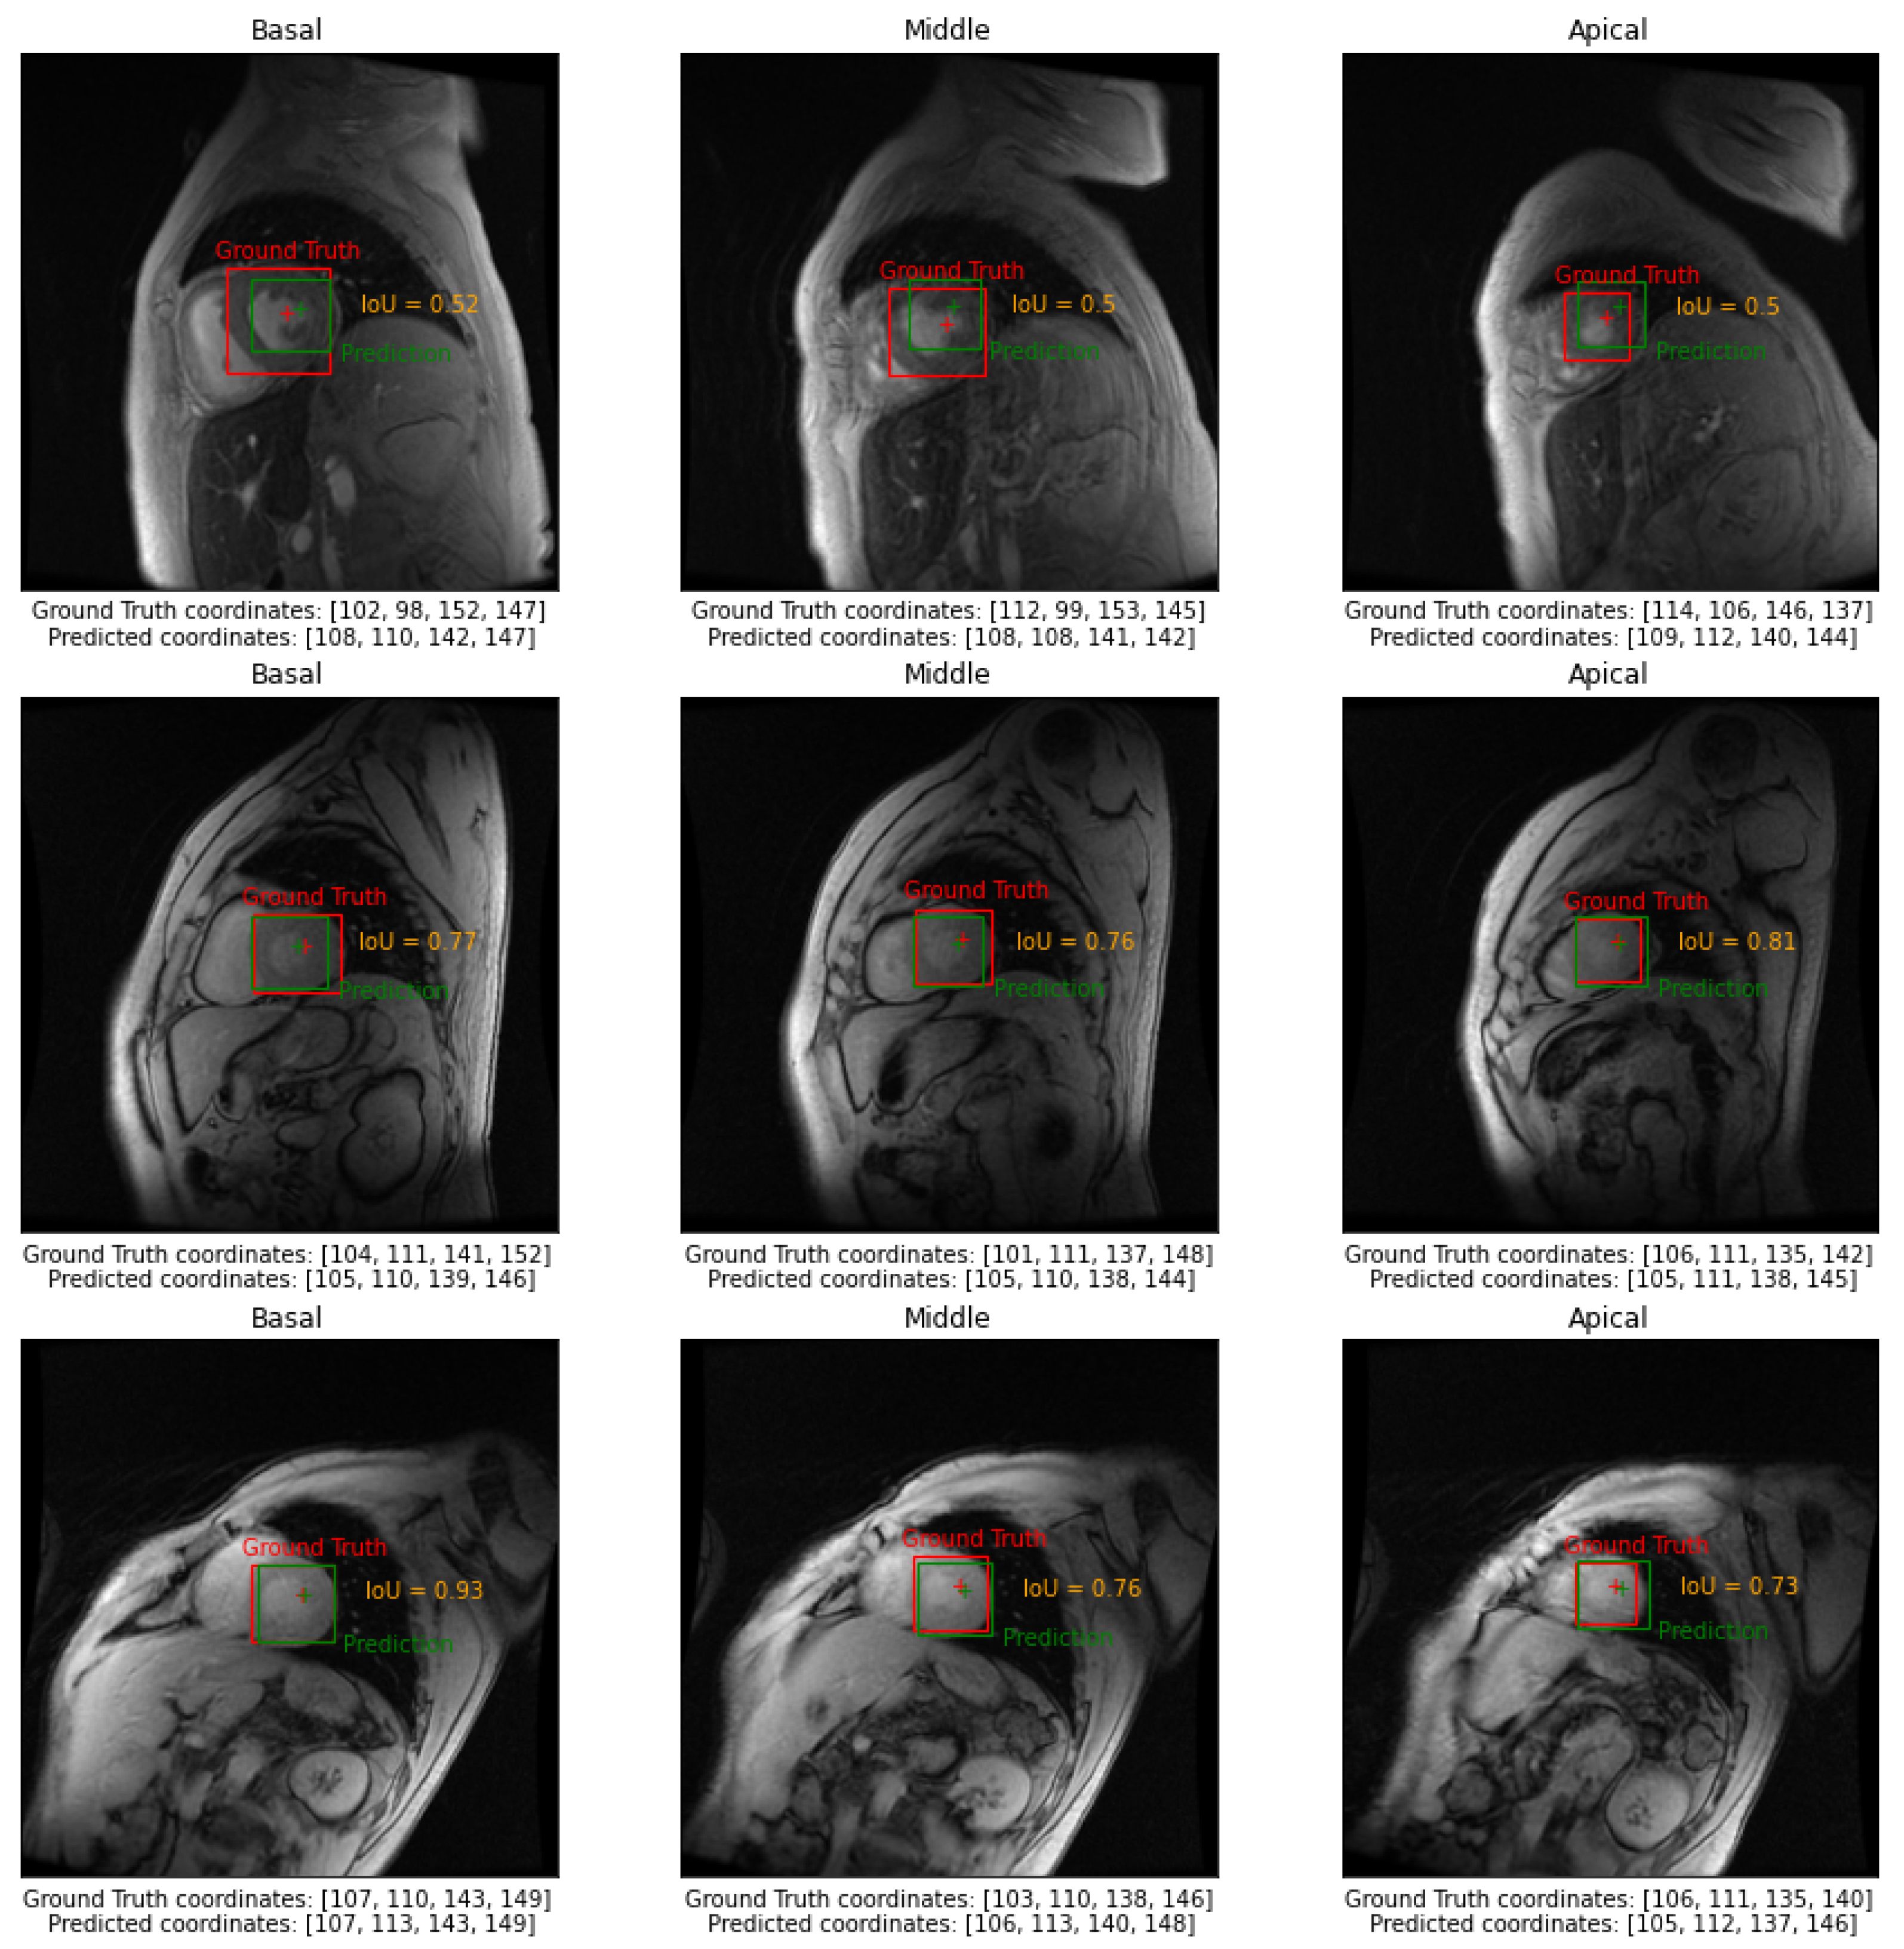

3. Results

| Slice | ||||||

|---|---|---|---|---|---|---|

| Basal | 0.69 ± 0.03 | 0.81 ± 0.02 | 7.12 ± 0.97 | 0.27 ± 0.03 | 0.31 ± 0.04 | 1.00 ± 0.00 |

| Middle | 0.71 ± 0.02 | 0.82 ± 0.02 | 6.52 ± 0.81 | 0.26 ± 0.03 | 0.31 ± 0.04 | 0.99 ± 0.00 |

| Apical | 0.63 ± 0.01 | 0.77 ± 0.01 | 6.68 ± 0.77 | 0.33 ± 0.04 | 0.42 ± 0.05 | 0.97 ± 0.01 |

| Global | 0.68 ± 0.02 | 0.80 ± 0.02 | 6.77 ± 0.81 | 0.29 ± 0.03 | 0.35 ± 0.04 | 0.99 ± 0.00 |